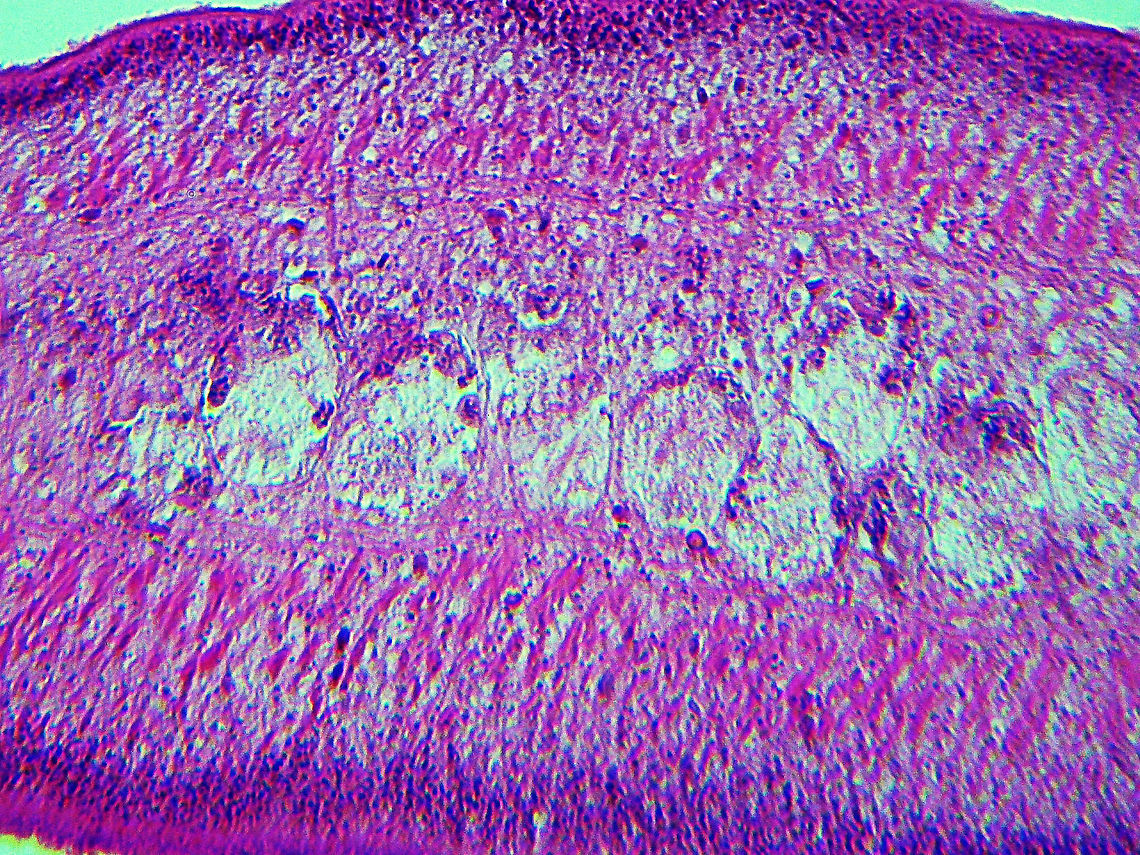

''Taenia pisiformis'', commonly called the rabbit tapeworm, is an endoparasitic tapeworm which causes infection in lagomorphs, rodents, and carnivores. Adult ''T. pisiformis'' typically occur within the small intestines of the definitive hosts, the carnivores. Lagomorphs, the intermediate hosts, are infected by fecal contamination of grasses and other food sources by the definitive hosts. The larval stage is often referred to as ''Cysticercus pisiformis'' and is found on the livers and peritoneal.. more